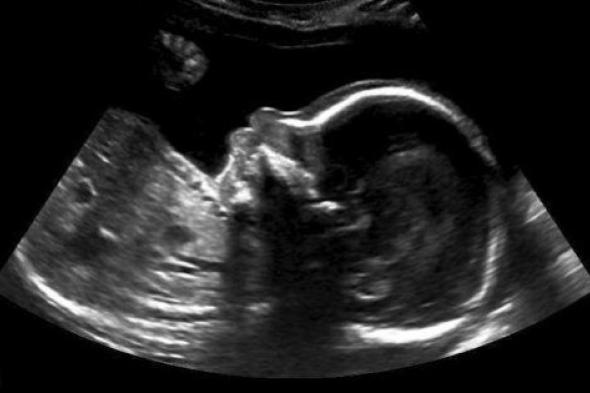

Image courtesy Nicole Kim

Todavía no ha nacido, pero este bebé canadiense tiene un mensaje para sus padres: quiere decirles que todo va a ir bien.

Nicole Kim, la madre, encontró este inspirador mensaje en la ecografía de la semana 20: un pulgar para arriba. Kim contó en la web del programa Today, de la NBC, que el mensaje del bebé llegó justo cuando su padre, Tony, lo acababan de echar del trabajo.

En una entrevista con el Calgary Herald, Kim contó también que el técnico de la clínica de Calgary donde hizo la ecografía le dio rápidamente al zoom y tomó la foto cuando vio al bebé con el pulgar levantado.